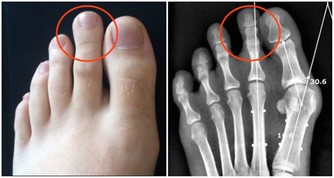

第一次手術我的左側甲狀旁腺就被拿掉了,但是我不知道,醫生也沒有醫囑。在那個年代也沒有補鈣的概念的。我記得大肆廣告補鈣是在95、96年,我87年做的手術時可沒人給我說過這個事情。幸好我右側的甲狀旁腺保留了,它的功能也有了代償。所以沒有發生過抽搐等現象。但是其實身體是出於缺鈣的症狀的,我的腳趾甲就沒長起來,只有兩個大腳趾有指甲。